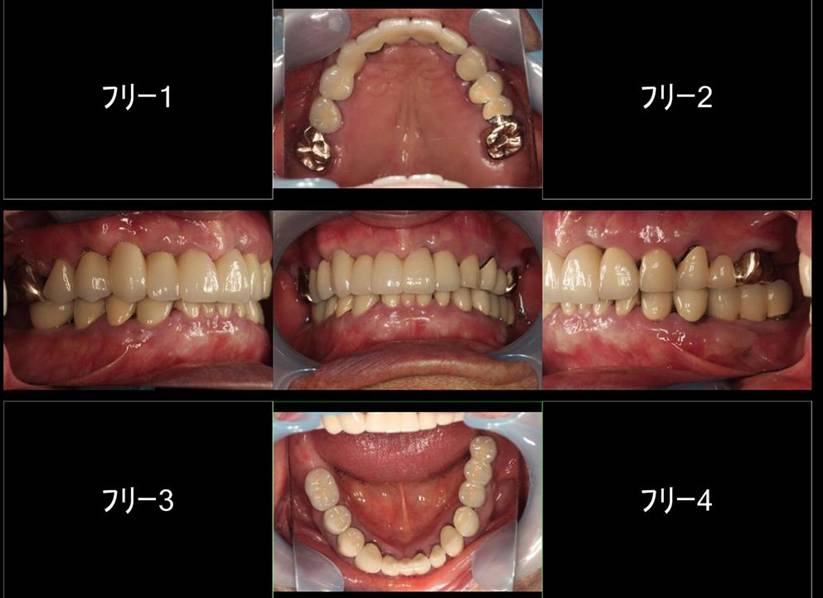

歯周病で抜歯せざるを得ず、インプラントを希望されたケース(使用インプラントはスプライン)

術前。すべての歯が歯周病の末期状態でブリッジ全体がうごいて噛めないとの訴え。右上の犬歯が腫れていました

固定式のブリッジが入っていましたが歯周病で動いています

下顎前歯部には歯石の沈着がみられます

術後。上部構造はハイブリッドレジンです。しっかり嚙めるようになり喜んでいただきました。

上顎

下顎

上部構造装着後6年。ハイブリッドレジンを使用したため、少し艶がなくなってきました。上部構造の材料には金属、ハイブリッドレジン、セラミックなどがあります。セラミックはきれいですが欠けやすいため、最近はフルジルコニアを使っています。

上顎 少しすり減ってきました。

下顎。12か月に一度メインテナンスをしています。

インプラント装着後6年。順調に経過しています。12か月毎のメインテナンスをしています。